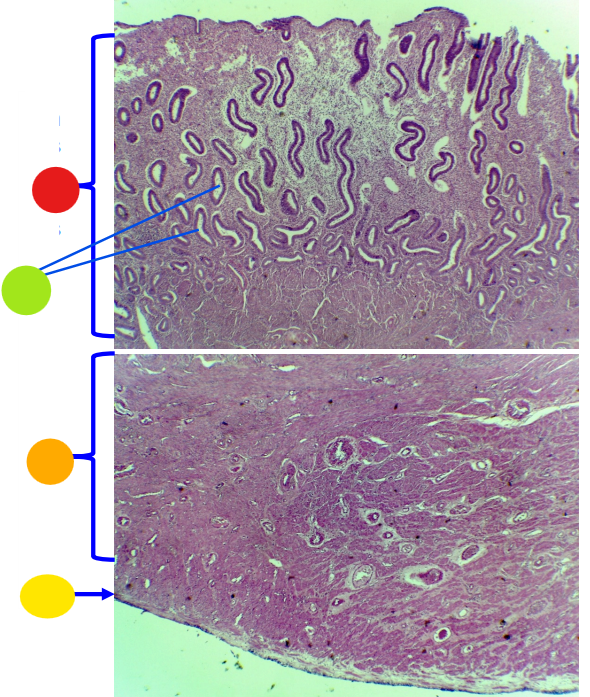

red

tunica albuginea

orange

primordial follicles

yellow

follicular cells

light green

primary oocyte

dark green

granulosa cells

light blue

primary follicles

what is this?

ovary

red

primordial follicles

red

primary follicles

red

tunica albuginea

orange

primary oocyte

yellow

primordial follicles

red

tunica albuginea

orange

primordial follicles

red

primary follicle

orange

secondary follicles

what is this

tertiary follicle